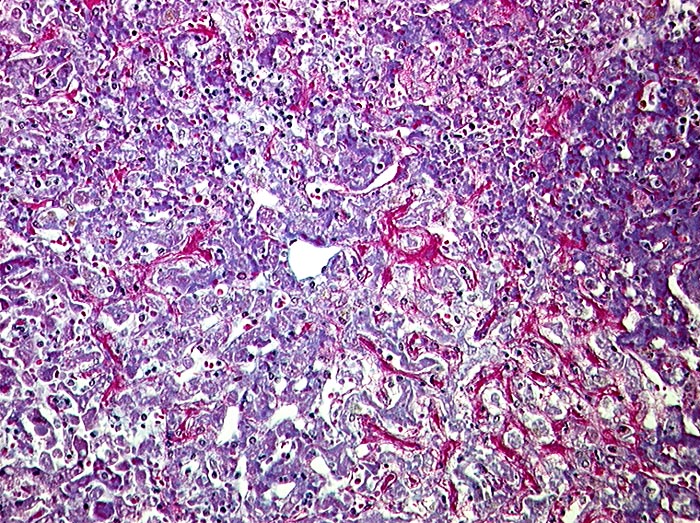

Subakute Stauung der Leber

Pathologischer Befund